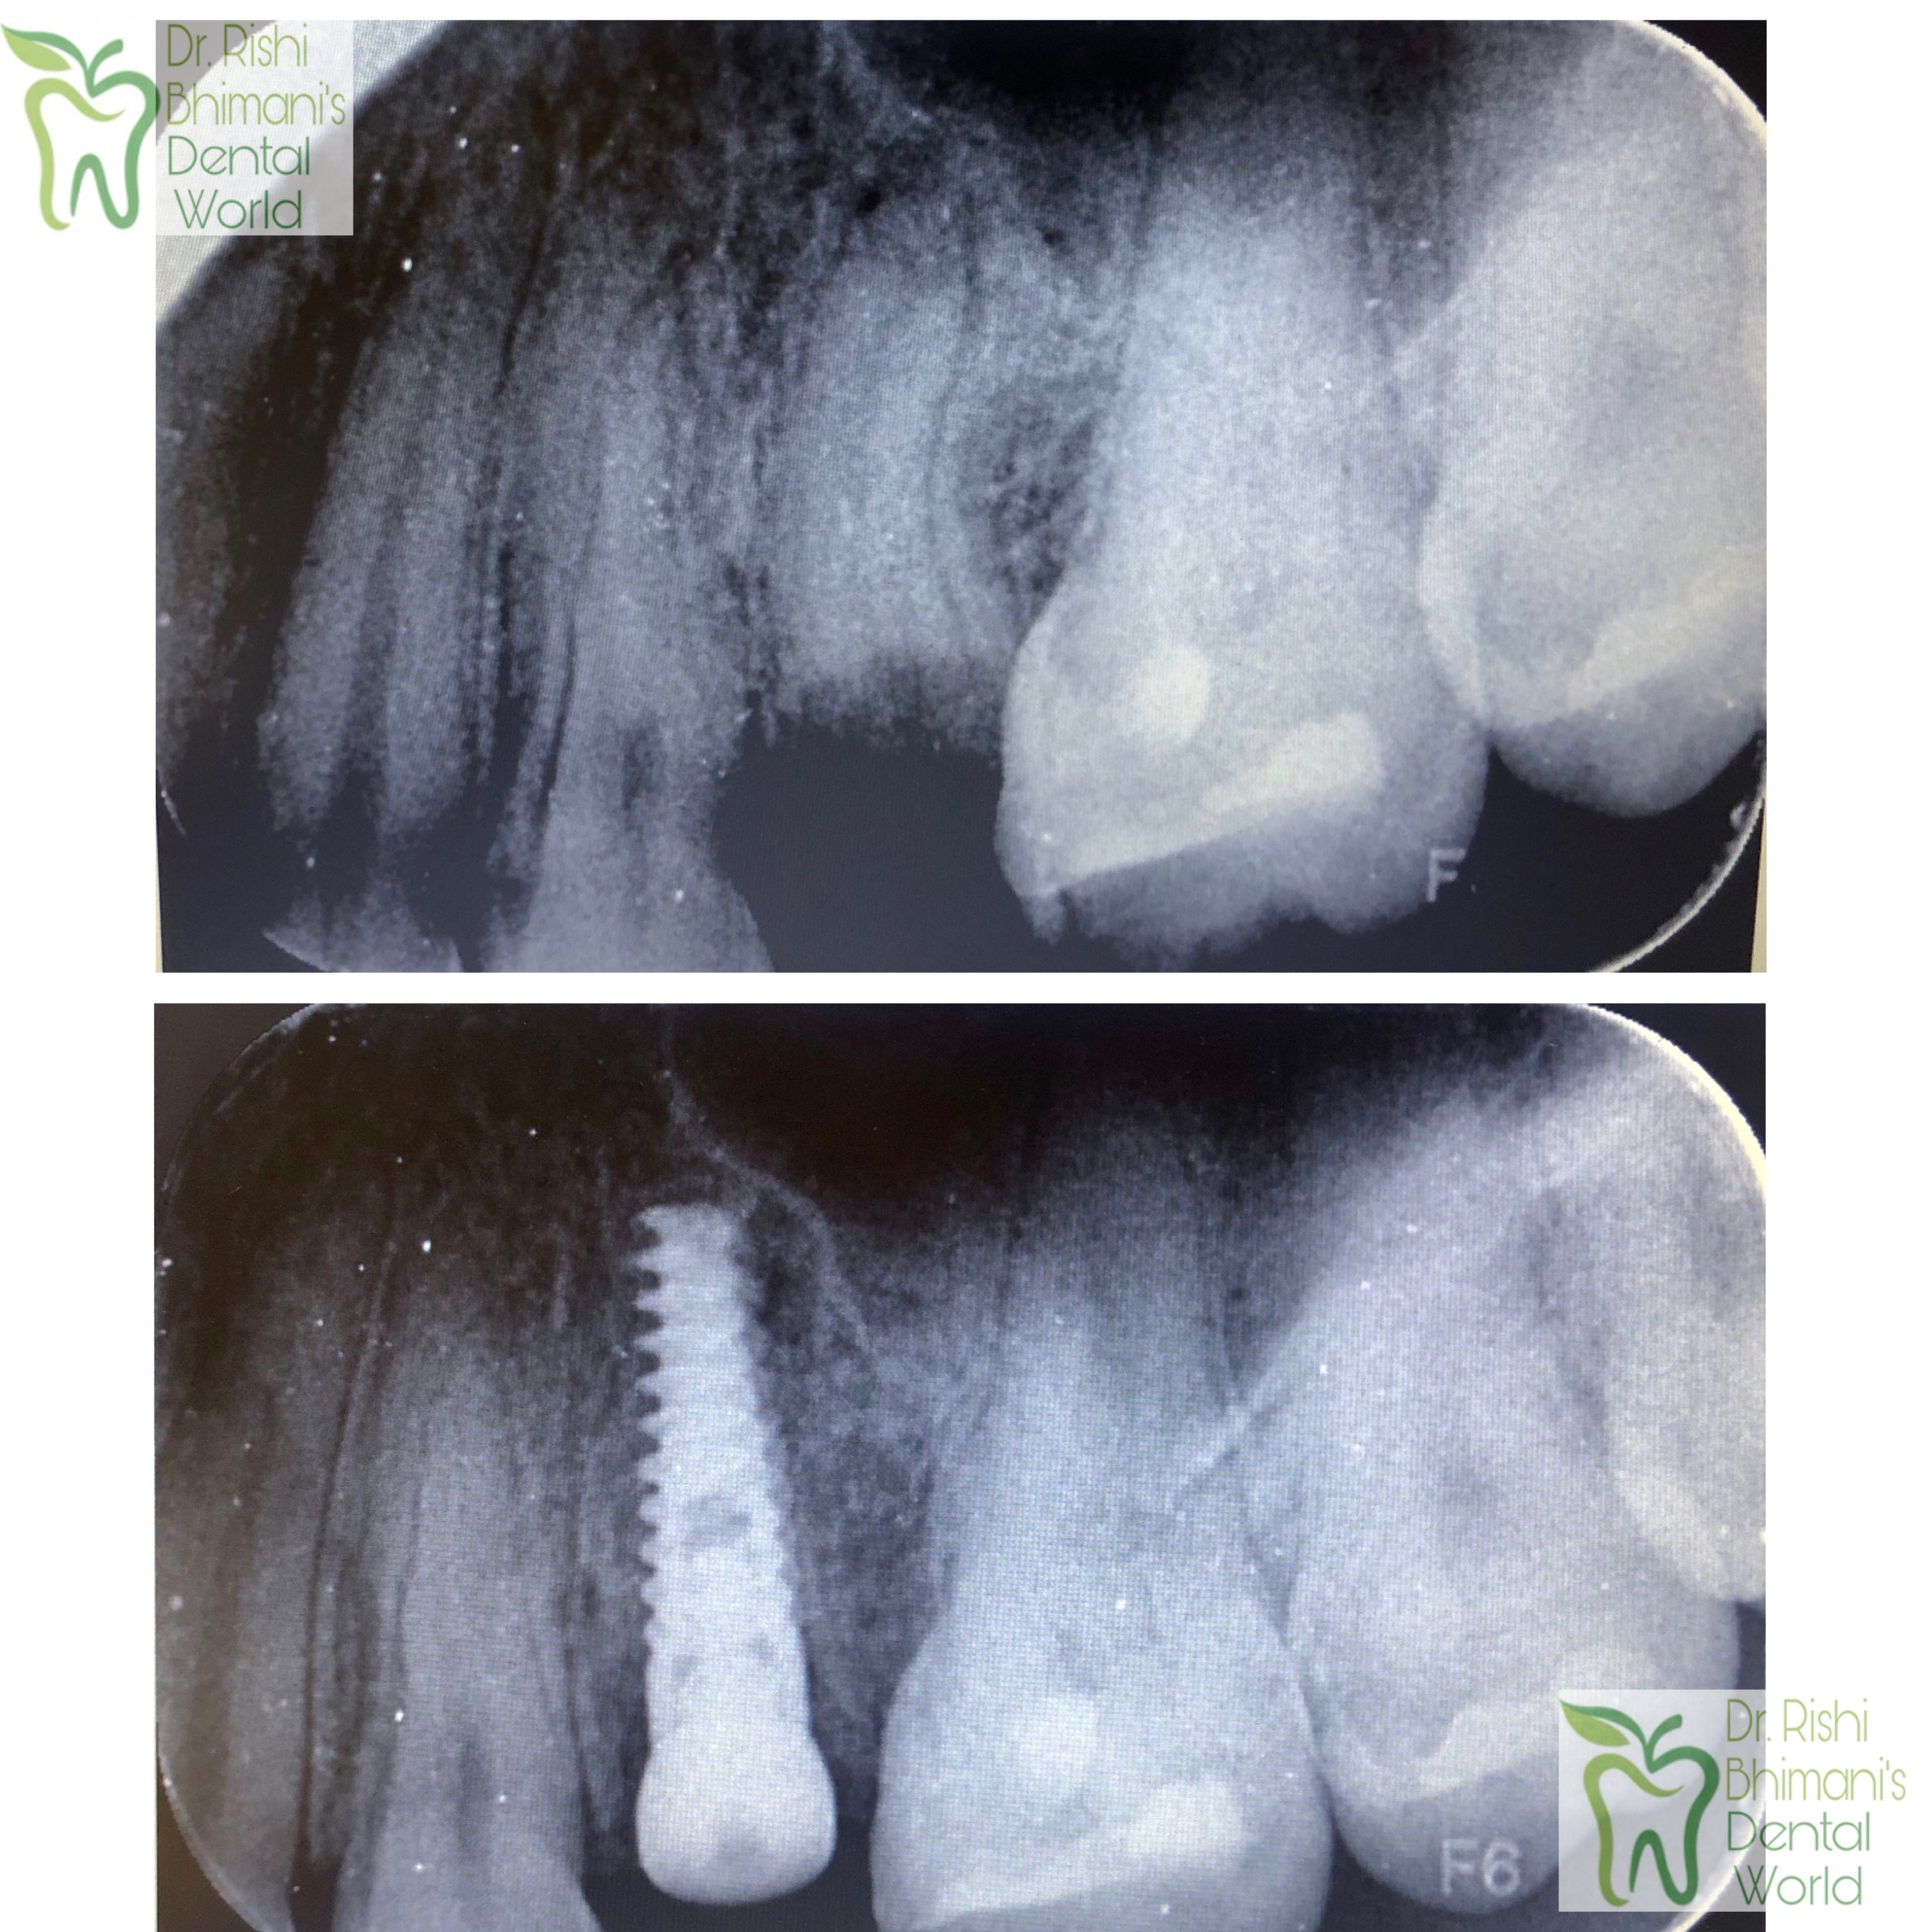

IMMEDIATE DENTAL IMPLANT DENTAL IMPLANTS can replace a single missing or broken tooth or multiple teeth. Dental Implants provide FIXED TEETH solutions and serve as a second set of permanent teeth. Broken teeth can be replaced by IMMEDIATE TOOTH IMPLANT within an hour. DENTAL IMPLANTS are safe and affordable and provide the best chewing efficiency, similar to natural teeth. Visit DENTIST IN VASHI, DENTIST IN NAVI MUMBAI at Dr. Rishi's dental clinic, Vashi for further queries.